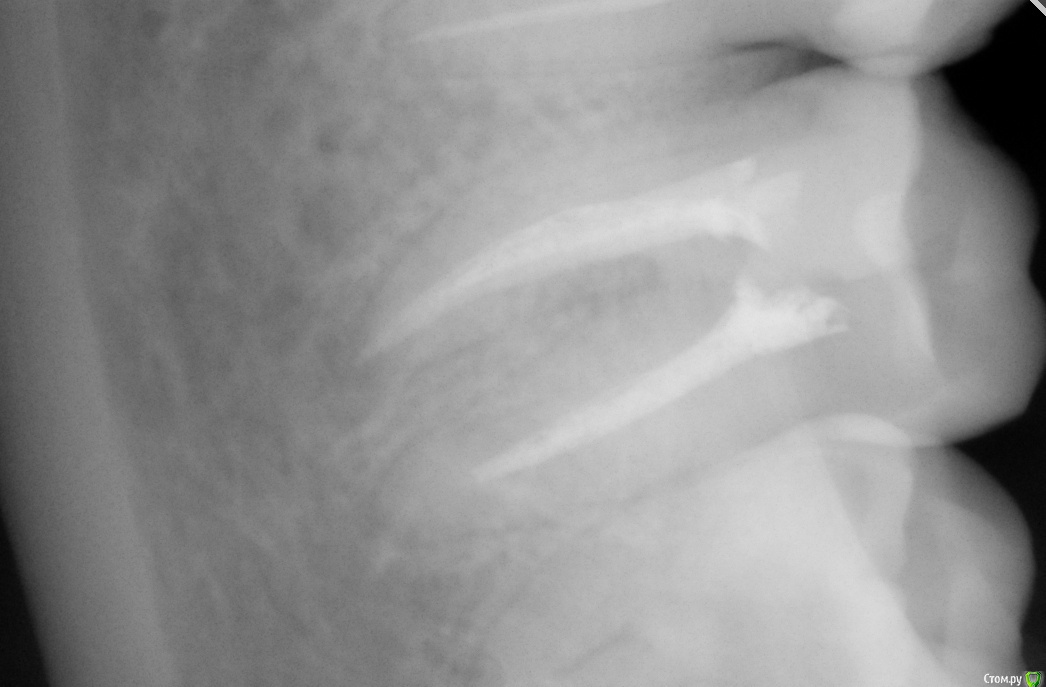

Jea Опубликовано 24 декабря, 2015 Поделиться Опубликовано 24 декабря, 2015 Добрый день! Помогите разобраться в сложившейся ситуации. Очень нужна оценка проведенного лечения сторонним экспертом. Хронология событий: 07.11 - первичный прием. Жалобы: ноющая боль в 7м левом нижнем зубе, носящая периодический характер, усиливающаяся в ночное время. Реакции на горячее/холодное, кислое/сладкое не было. Установленный диагноз: пульпит. Проведенные манипуляции: удаление нервов. 14.11- Пломбировка каналов. 21.11 - установка постоянной пломбы. 20.12 - повторное обращение по проведенному раннее лечению. Жалобы: боль после лечения не проходящая в течении месяца (нояющая, усиливающаяся в ночное время, при надкусывании). Есть левой стороной я не могла. Диагноз: воспалительный процесс в зубе. Манипуляции: распломбировка каналов, закладка лекарства, временная пломба. В течение 2х дней сильные постпломбировочные боли. Вечером 22.12 опухла десна. 23.12 прием по осложнениям после лечения, в ходе которого выяснилось, что во время распломбировки каналов зуб треснул и внесенное в канал лекарство вылилось в десну. Предложенный план лечения: удаление+ имплантация. Необходима оценка качества проведенного лечения и прогноз на дальнейшее лечение зуба. Прикрепляю все снимки, сделанные в ходе лечения. Благодарю! Ссылка на комментарий

St. Опубликовано 24 декабря, 2015 Поделиться Опубликовано 24 декабря, 2015 А также действительно ли он треснул (видно ли это на снимках)? Да, похоже на то. Ссылка на комментарий

Бендер Опубликовано 25 декабря, 2015 Поделиться Опубликовано 25 декабря, 2015 Зуб не жилец, к сожалению Ссылка на комментарий